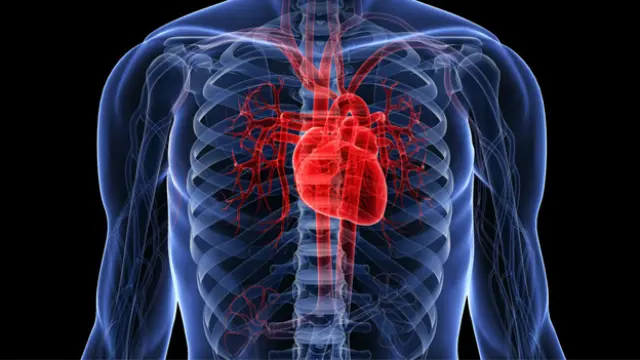

Para llevarlo a cabo tuvieron que utilizar 73 corazones del banco de órganos de la ciudad. Ninguno de ellos era transplantable así que no se causó perjuicio a personas vivas. De ellos extrajeron las células que forman los tejidos de las paredes del corazón para quedarse con la matriz extracelular. Esta matriz es el “recipiente” donde inyectaron las células madre del tejido cardiaco, conocido como miocardio.

En apenas unos días esas células madre consiguieron crecer, convirtiéndose en tejidos. A los catorce días estos tejidos eran ya capaces de contraerse ante impulsos eléctricos. Nada indicó problema alguno con los tejidos nuevos, lo que significa que son totalmente funcionales.

La regeneración del tejido cardiaco demuestra que es posible regenerar órganos, al menos parcialmente. Aun así, los investigadores se muestran cautos a corto plazo: “Regenerar un corazón completo es una meta que aún queda a muchos años de distancia, así que por el momento trabajamos en parches de miocardio que puedan regenerar los tejidos dañados por infartos y otros problemas cardiacos” afirma Jacques Guyette, investigador del Hospital de Massachusetts.